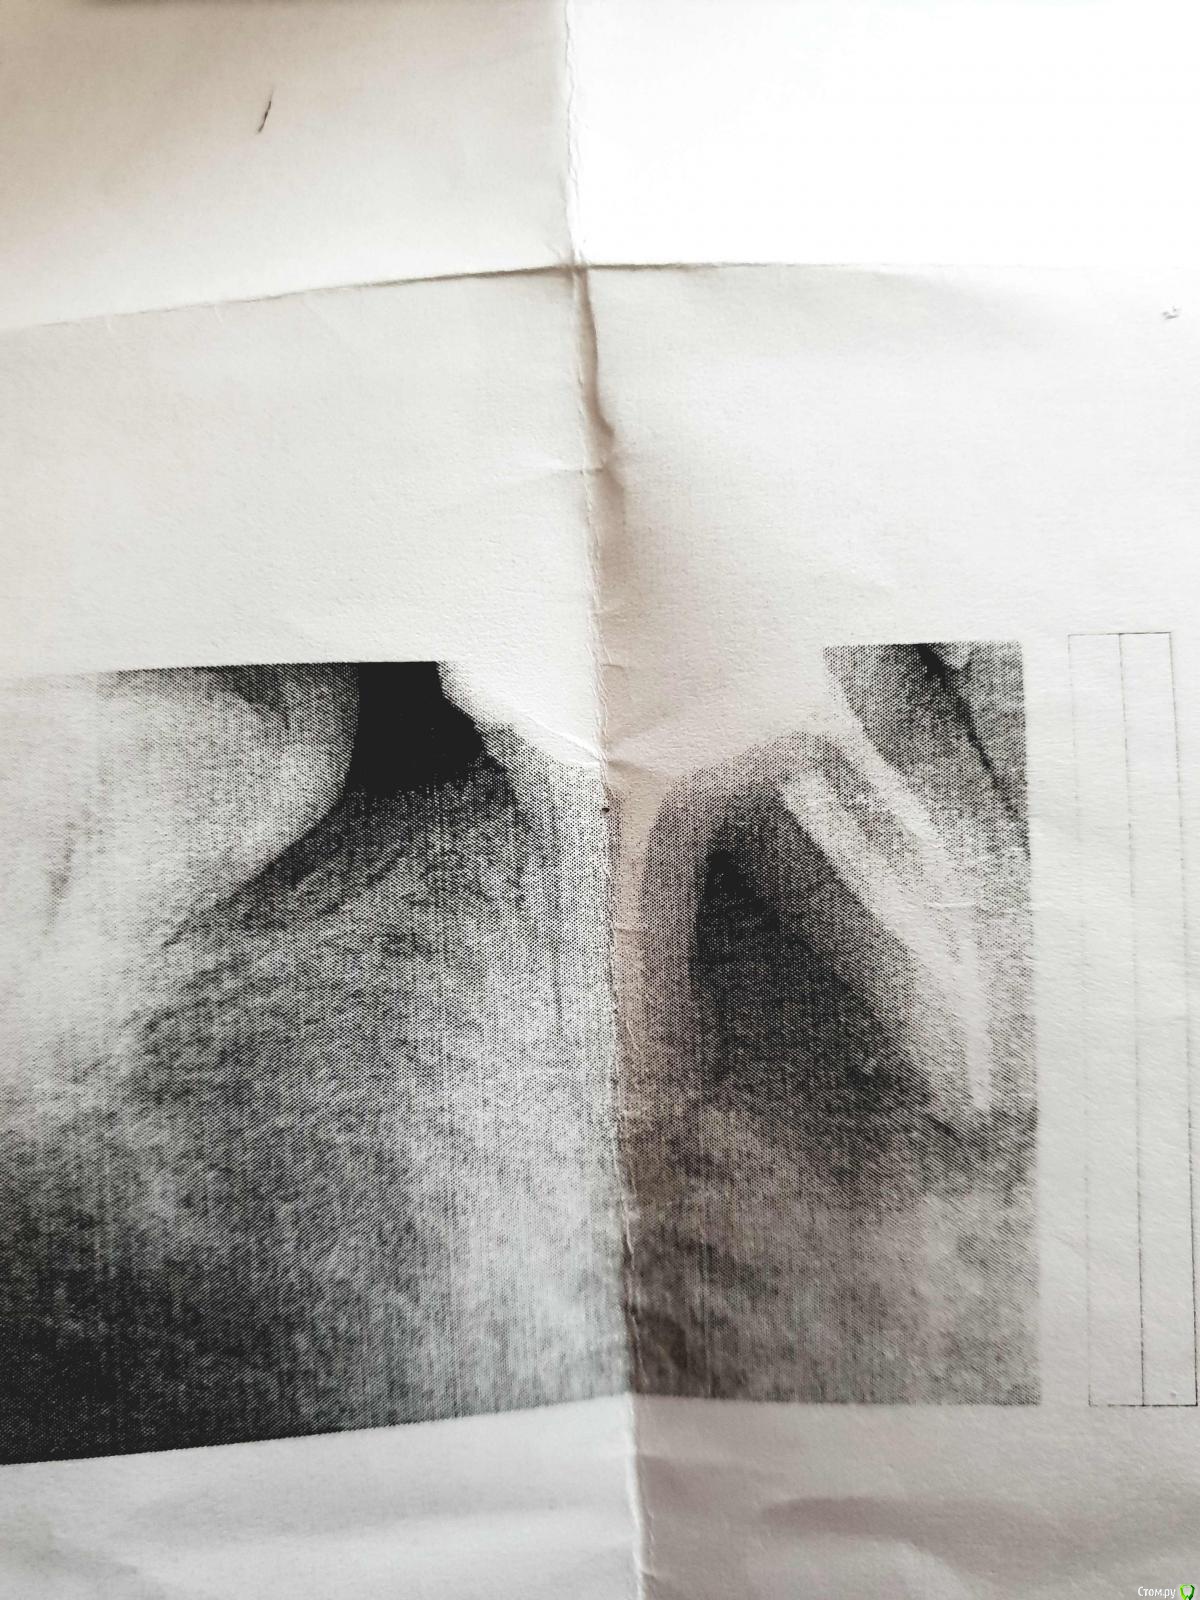

vorand Опубликовано 29 декабря, 2018 Поделиться Опубликовано 29 декабря, 2018 (изменено) Добрый день.Сегодня был на плановом осмотре у врача. Ничего не болели и не болит. Года два назад перелечивал пульпит. Сегодня сделал снимок, доктор сказал, что обширная киста между корнями правой нижней 6. На рентгене между корнями все черное. И нужно этот зуб удалять. Скажите, можно ли в таких случаях ставить импланты? Или придется ставить мост. 7 соседней нет уже лет 6, на 5 стоит коронка. Изменено 29 декабря, 2018 пользователем vorand Ссылка на комментарий

vorand Опубликовано 29 декабря, 2018 Автор Поделиться Опубликовано 29 декабря, 2018 (изменено) Вот фото рентгена. Прикрепил к первому сообщению. Изменено 29 декабря, 2018 пользователем vorand Ссылка на комментарий

___49___ Опубликовано 4 января, 2019 Поделиться Опубликовано 4 января, 2019 Сейчас был в другой клинике, предлагают попытаться сохранить зуб. Перелечиванием каналов. Как вы думаете, возможно ли это?снимок плохого качества. Ссылка на комментарий

Дмитрий М Опубликовано 18 января, 2019 Поделиться Опубликовано 18 января, 2019 судя по снимку перелечивать нет смысла еще не определился ни с системой имплантов не выбирайте систему имплантов, выбирайте доктора которому доверяете 1 Ссылка на комментарий